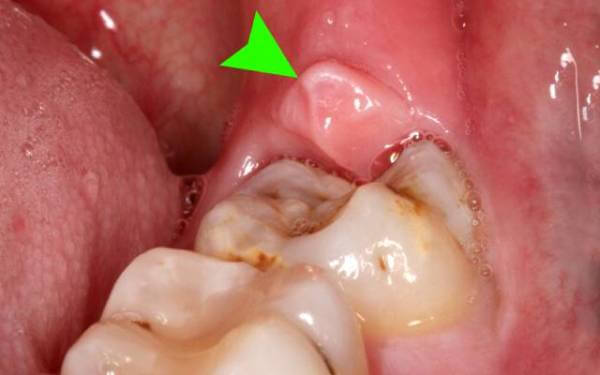

Неполное прорезывание приводит к формированию десневого капюшона – складки десны над зубом. Особенностью этого образования является то, что в него часто набивается пища, которую очень сложно вычистить зубной щеткой.

При обсеменении остатков пищи микроорганизмами развивается очень неприятное заболевание – перикоронарит.

- Иногда прорезывающийся зуб накрывает своеобразный «капюшон» из разросшейся слизистой. Под ним скапливаются остатки пищи и размножаются бактерии.

Этот процесс приводит не только к болезненности и отеку. Появляется неприятный запах изо рта и затруднение при глотании.

- Вздутие десны в виде «капюшона» над еще непрорезавшимся зубом. Если процесс роста затягивается, развивается воспаление мягких тканей после проникновения бактерий под «капюшон».

Острая боль в десне и челюсти могут возникать, если зуб мудрости лезет неправильно, притесняя корни соседа. Или если в отверстие десны попадает зубной налет и в тканях, окружающих зуб, развивается инфекция. Это явление называется перикоронаритом и требует незамедлительного обращения к стоматологу.